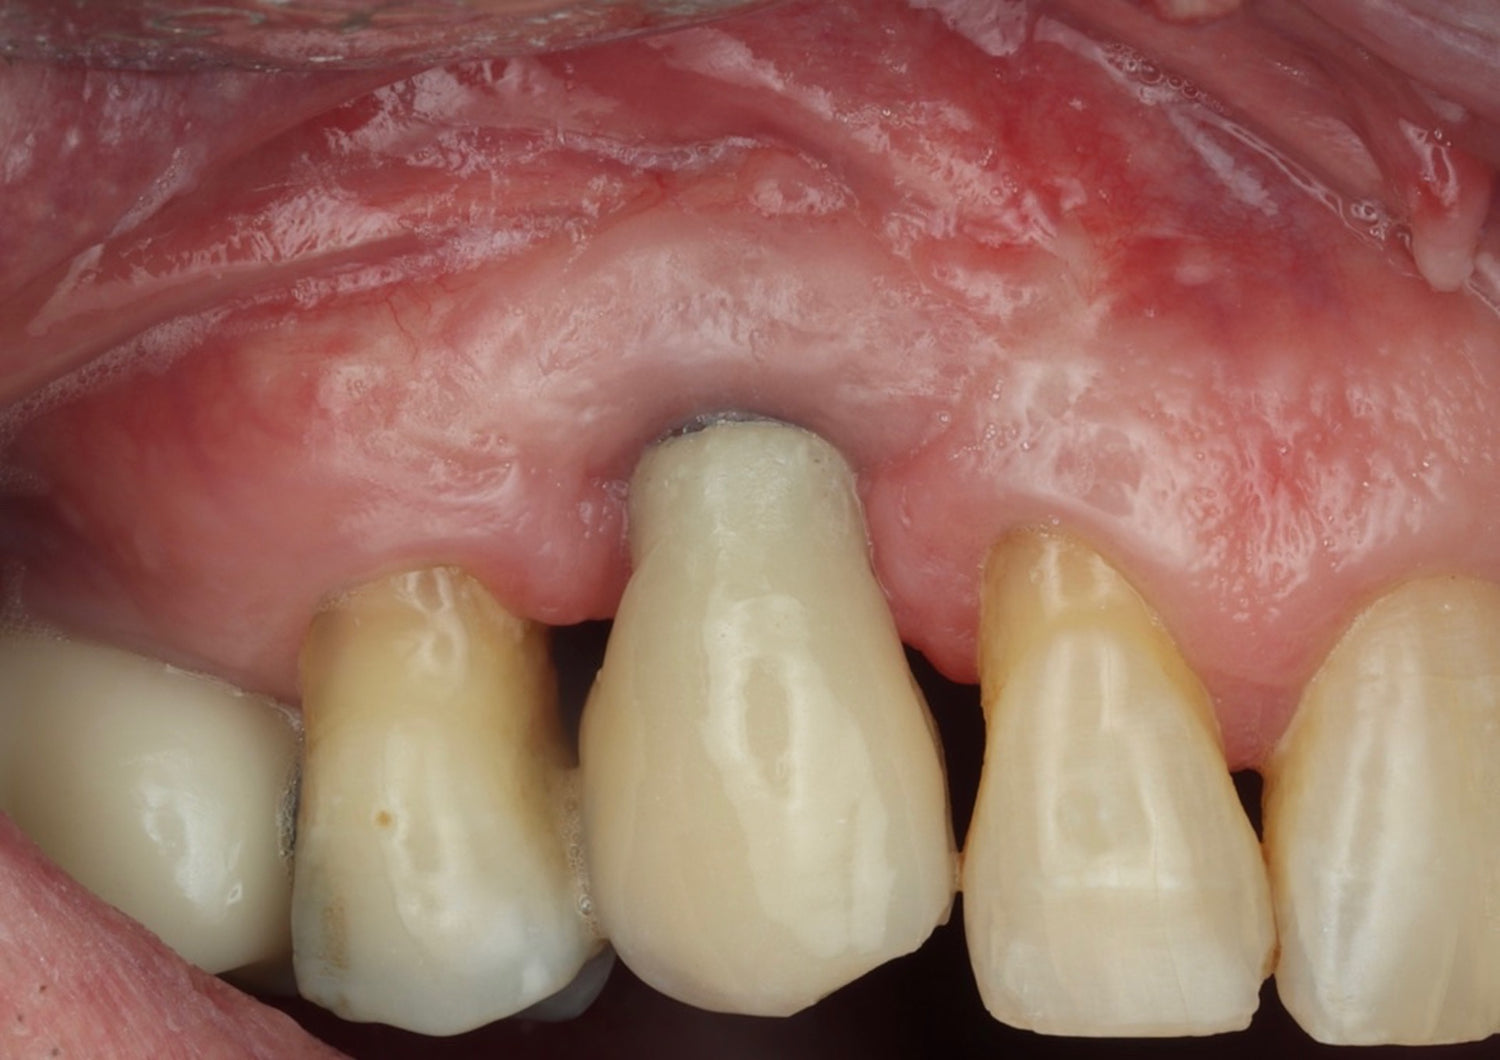

- Explore the science behind Partial Extraction Therapy and understand its emergence as the gold standard in modern implantology

- Master Partial Extraction Therapy through systematic, step-by-step instruction and hands-on practice

- Socket shield,

- Root submergence,

- Socket shield modifications